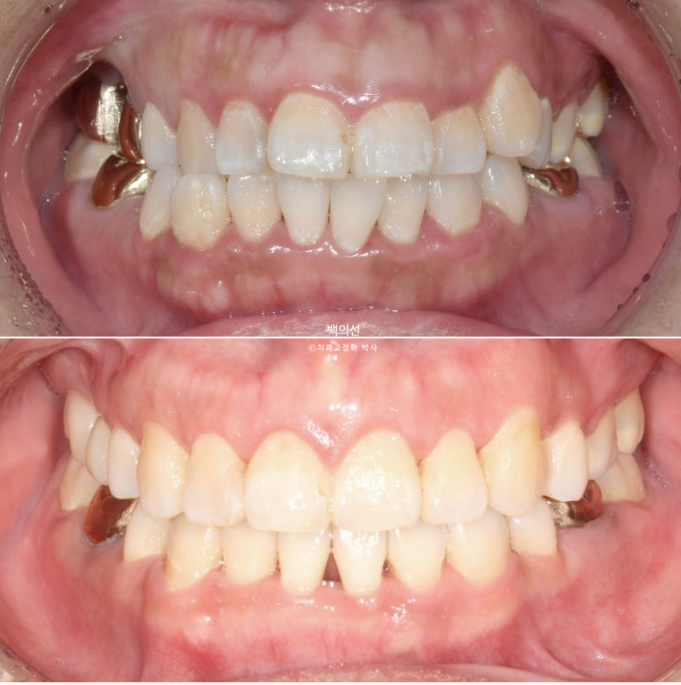

이후 발치공간 폐쇄 및 교정용 나사인 미니스크류를 이용한 거미스마일 개선 치료를 더 진행 후 25년 6월, 치료를 마무리 했습니다. 총 치료기간은 2년 6개월입니다.

25.06

교정과 크라운치료를 모두 마친 후 클리피씨 브라켓을 제거한 모습입니다.

짧은 앞니 길이를 회복하고자 위 앞니 4개에 잇몸성형을 합니다.

잇몸성형 직후 모습입니다. 잇몸성형은 <성형> 글자가 들어가니 무섭게 느껴지지만, 실제로는 피가 나거나 하지 않습니다.

잇몸성형 후 일주일간의 회복기간을 거친 후 모습입니다.

중심선을 잘 맞으며 아래턱 비대칭에 의한 반대교합은 해소되었습니다. 교정으로 턱뼈 자체를 바꿀 수는 없지만 최소한 치아중심선을 맞춰줄 수 있습니다.

아쉬운 점으로는 아래 앞니 블랙트라이앵글입니다.

치간삭제를 더 하면 블랙트라이앵글 사이즈를 줄일 수 있지만, 환자분이 무리한 치간삭제를 원치 않아 많은 양은 진행하지 않았습니다.

교합은 1급 교합관계를 보이며 물샐틈없이 좋습니다.

교정과 잇몸성형으로 거미스마일은 개선되었습니다.